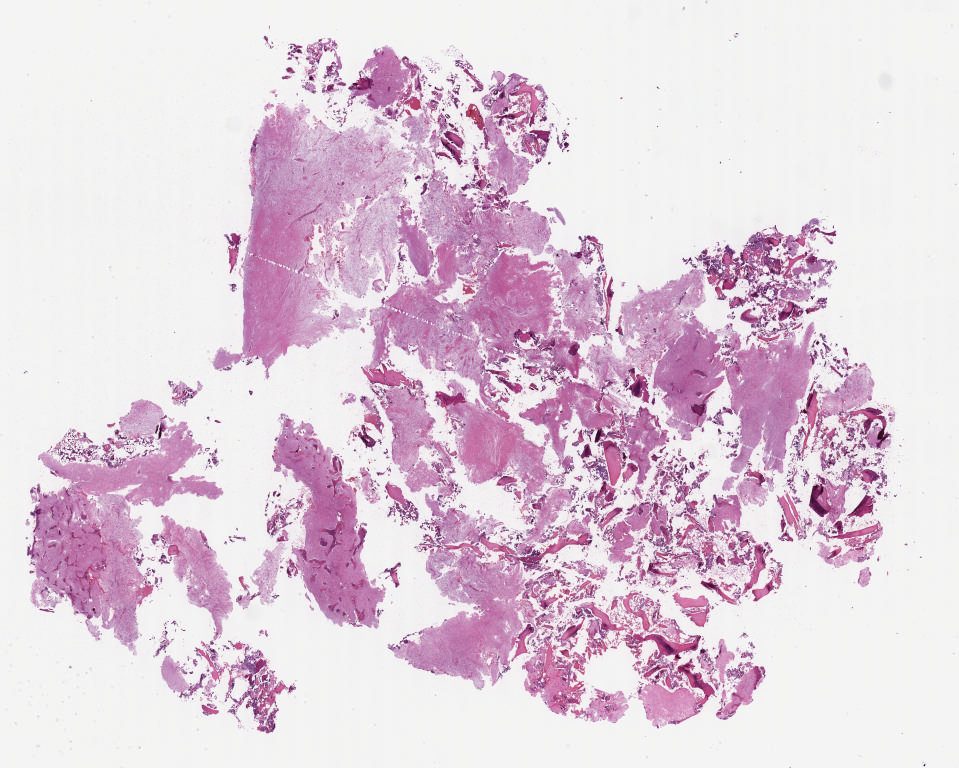

Case3.svs

127488

x

87327

@

40X